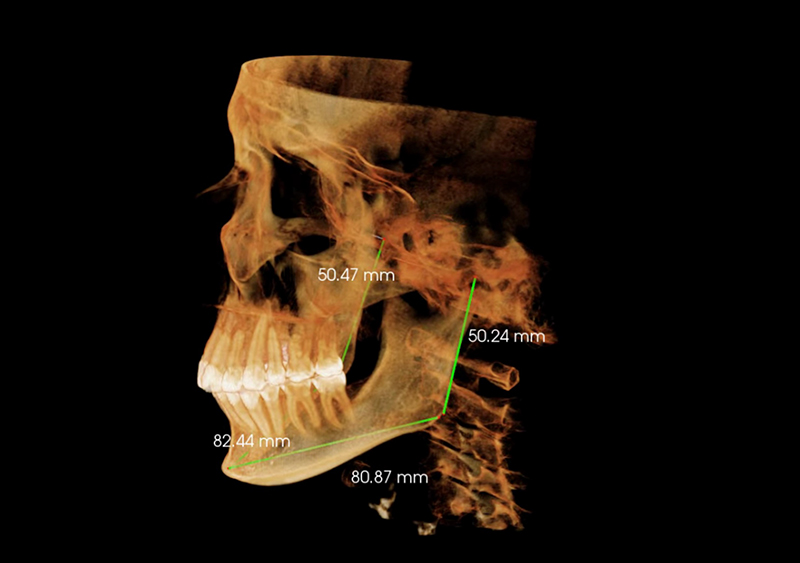

Estudio de Simetría

Nos permite analizar las distintas estructuras craneofaciales y su

relación entre si, para determinar biotipos faciales y predecir líneas de

crecimiento y desarrollo, además de posibles compensaciones